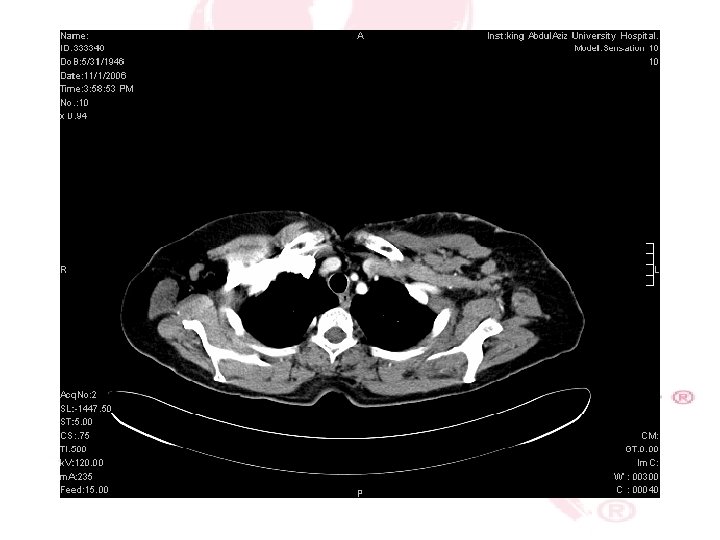

CT SCAN CHEST , ABDOMEN &PELVIS